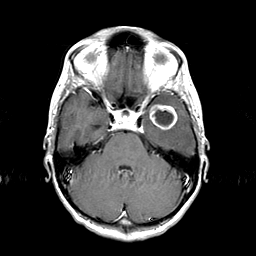

Metastatic bronchogenic carcinoma: T1-weighted MR -- Slice #6

[Home][Help][Clinical] Slice 6